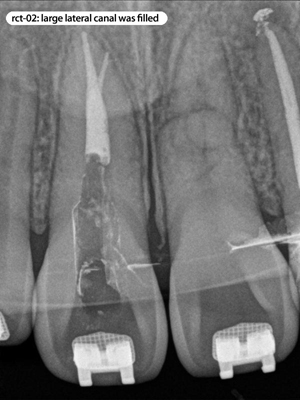

Root Canal Cases